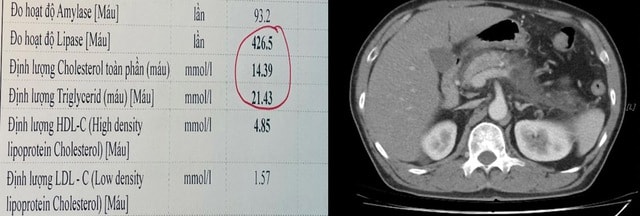

Theo bác sĩ Tô Hoàng Dương - Phó Trưởng khoa Hồi sức tích cực và chống độc, Bệnh viện Hữu Nghị, đây là một trường hợp đã có tiền sử viêm tụy cấp cách đây 02 năm, đái tháo đường và rối loạn mỡ máu. Bệnh nhân nhập viện tại khoa Cấp cứu trong tình trạng đau bụng giữ dội vùng thượng vị, xét nghiệm có tình trạng men tụy và mỡ máu tăng rất cao, gấp khoảng 12 lần giá trị cho phép (Cholesterol là 14.3 mmol/L và Triglyceride là 21.43 mmol/L). Trên hình ảnh phim chụp cắt lớp vi tính ổ bụng cho thấy tụy đã bị tổn thương nặng, thâm nhiễm kèm tụ dịch xung quanh.